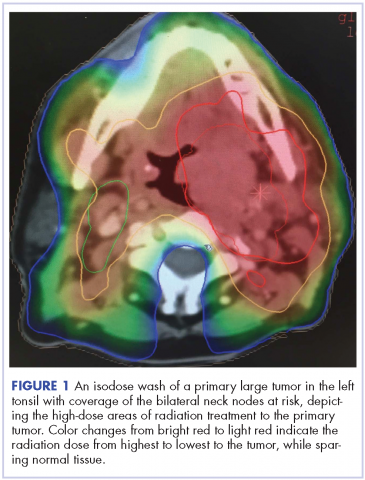

Despite significant treatment advances, the management of advanced squamous cell carcinoma of the tonsil remains challenging. Historically, surgery was considered the standard of care for patients with tonsillar carcinoma with or without postoperative adjuvant radiotherapy. In locally advanced tonsillar carcinoma, extensive surgery with major tissue reconstruction was necessary, leading to speech dysfunction, cosmetic deformities, and difficulties in swallowing, all of which are detrimental to patient quality of life.13 Given the critical role of the oropharynx in speech and swallowing, nonsurgical therapy with organ-preserving chemoradiation has gained a greater role in the treatment of tonsil carcinoma.13 Over the past decade, innovations in radiation therapy techniques have led to the introduction of intensity-modulated radiation therapy (IMRT) and image-guided radiation therapy (IGRT) for the treatment of various cancers including tonsillar carcinoma.14,15 IMRT is an advanced mode of conformal high-precision radiotherapy that uses computer-controlled multiple small radiation beams of varying intensities to deliver precise radiation doses to the target tissues while sparing adjacent healthy tissues.14 By incorporating three-dimensional computed-tomography (CT) or positron-emission–tomography (PET) imaging technology, IMRT allows the radiation dose to conform more precisely to the three-dimensional shape of the tumor while modulating the intensity of the radiation beam and minimizing its dose to those adjacent sensitive and unaffected organs. IGRT uses a range of two-, three-, and four-dimensional imaging techniques that improve the precision and accuracy of the delivery of the radiation dose to the targeted tumor tissue while minimizing the dose to the surrounding normal tissue during the course of radiation therapy (Figure 1). In this report, we present challenging cases of advanced tonsillar carcinoma and describe our experience in managing the disease using a hyperfractionated IMRT-IGRT based three-dimensional conformal radiation therapy protocol with concurrent chemotherapy.